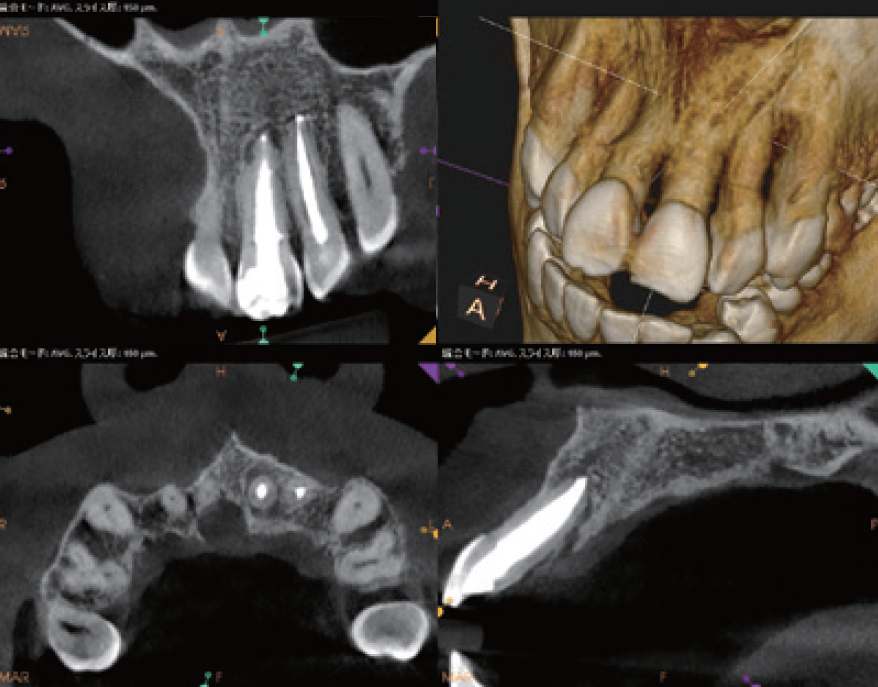

臨床症例3 その4

左上1番の根尖部にMTA製剤充填時のCBCT像

唇側皮質骨は大きく開窓し、根尖病変の大きさが鼻腔底付近まで広がっていることが確認できる

臨床症例3 その5

術後1年のCBCT像

根尖周囲に見られた根尖病変はほぼ消失し、唇側皮質骨の開窓も改善したことが認められる